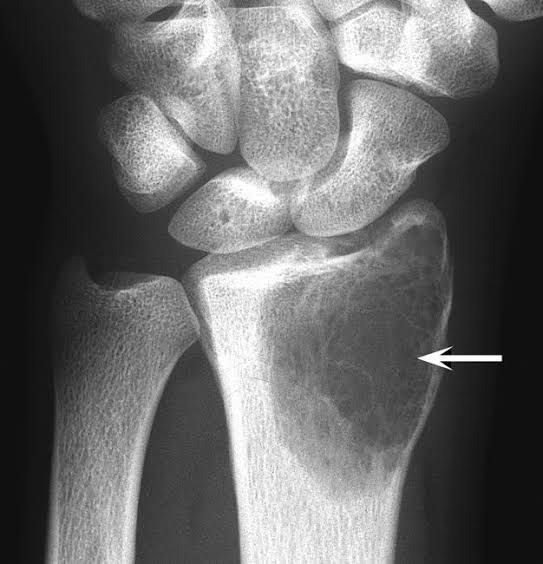

A giant cell tumor is a rare, aggressive non-cancerous tumor. It usually develops near a joint at the end of the bone. Most occur in the long bones of the legs and arms. Giant cell tumors most often occur in young adults when skeletal bone growth is complete. The exact cause of giant cell tumors remains unknown.